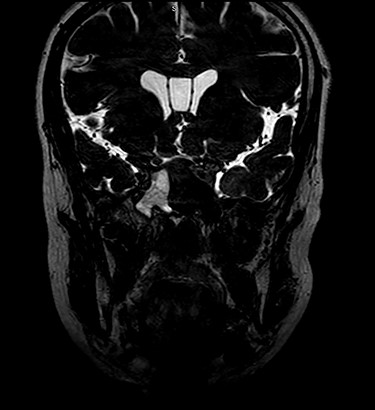

Patient underwent sinus computed tomography (CT), which demonstrated opacification of the right sphenoid sinus (Fig. 2). Brain MRI showed possible cerebrospinal fluid (CSF) leak at the right sphenoid sinus (Fig. 3). Lumbar puncture was done and fluid sent for analysis to rule out meningitis.

Coronal MRI of brain, T2 weighted image, showing opacification of right sphenoid sinus.